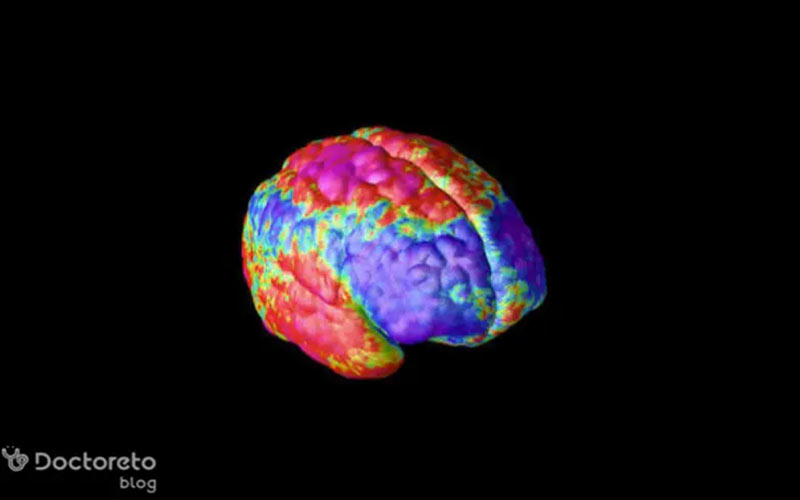

امواج مغزی در نوار مغز تشنج بسته به محلی که فعالیت غیرطبیعی از آن آغاز میشود، تشنج فوکال یا ژنرالیزه است. تشنجهای کانونی یا فوکال ابتدا در یک ناحیه مشخص از مغز شروع شده و ممکن است به مناطق دیگر گسترش یابند. در حالی که تشنجهای ژنرالیزه از ابتدا نواحی وسیعی از هر دو نیمکره را درگیر میکنند. شناخت محل انتشار تشنج در نوار مغز به پزشکان کمک میکند تا نوع تشنج، مسیرهای انتشار و گزینههای درمانی مناسب را تعیین کنند و پیشبینی دقیقی از روند بیماری داشته باشند. برای تشخیص تشنج در نوار مغز و تفسیر آن میتوانید از بهترین دکتر مغز و اعصاب و نورولوژی ایران مشاوره بگیرید.

تشنجهای کانونی یا تشنج فوکال به فعالیت الکتریکی غیر طبیعی محدود به یک ناحیه از یک نیمکره مغزی اشاره دارند. این نوع تشنجها ممکن است در هر ناحیهای از مغز شروع شوند و بسته به محل شروع، علائم بالینی متفاوتی ایجاد کنند؛ مثلاً در تشنجهایی که از لوب تمپورال یا لوب پیشانی منشا میگیرند، اختلالات حسی، حرکتی یا تغییرات شناختی دیده میشود. نوار مغز در این موارد الگوهایی از فعالیت غیر طبیعی را نشان میدهد که تنها در لایههای الکترودهای نزدیک به ناحیه درگیر دیده میشوند و اغلب با موجهای تیز (spikes) یا Sharp wave همراه هستند.

فعالیت الکتریکی کانونی میتواند در طول زمان به نواحی دیگر گسترش یابد و شکل گستردهتری به خود بگیرد؛ به همین دلیل گاهی تشخیص دقیق محل شروع نیازمند تحلیل ویدیویی همزمان با نوار مغز (Video-EEG) است. تشخیص کانون و مسیر انتشار میتواند در تعیین گزینههای درمانی، از جمله دارودرمانی یا جراحی، نقش مهمی داشته باشد.